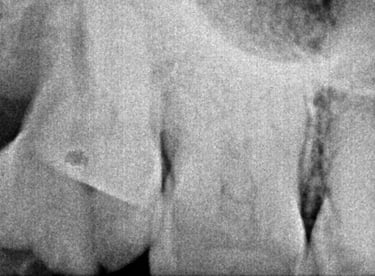

Root Canal Treatment near Shyamal, Ahmedabad

Before

After

All images shown here represent real clinical cases treated at our dental clinic with patient consent.

At Shree Dental Care, we focus on gentle, precise, and well-planned root canal treatment to remove infection, relieve pain, and preserve your natural tooth structure.

Patients from Shyamal and nearby areas of Ahmedabad visit our clinic for comfortable root canal procedures carried out using modern techniques and strict hygiene protocols. The treatment helps eliminate infection from inside the tooth, prevents further damage, and restores normal chewing function.